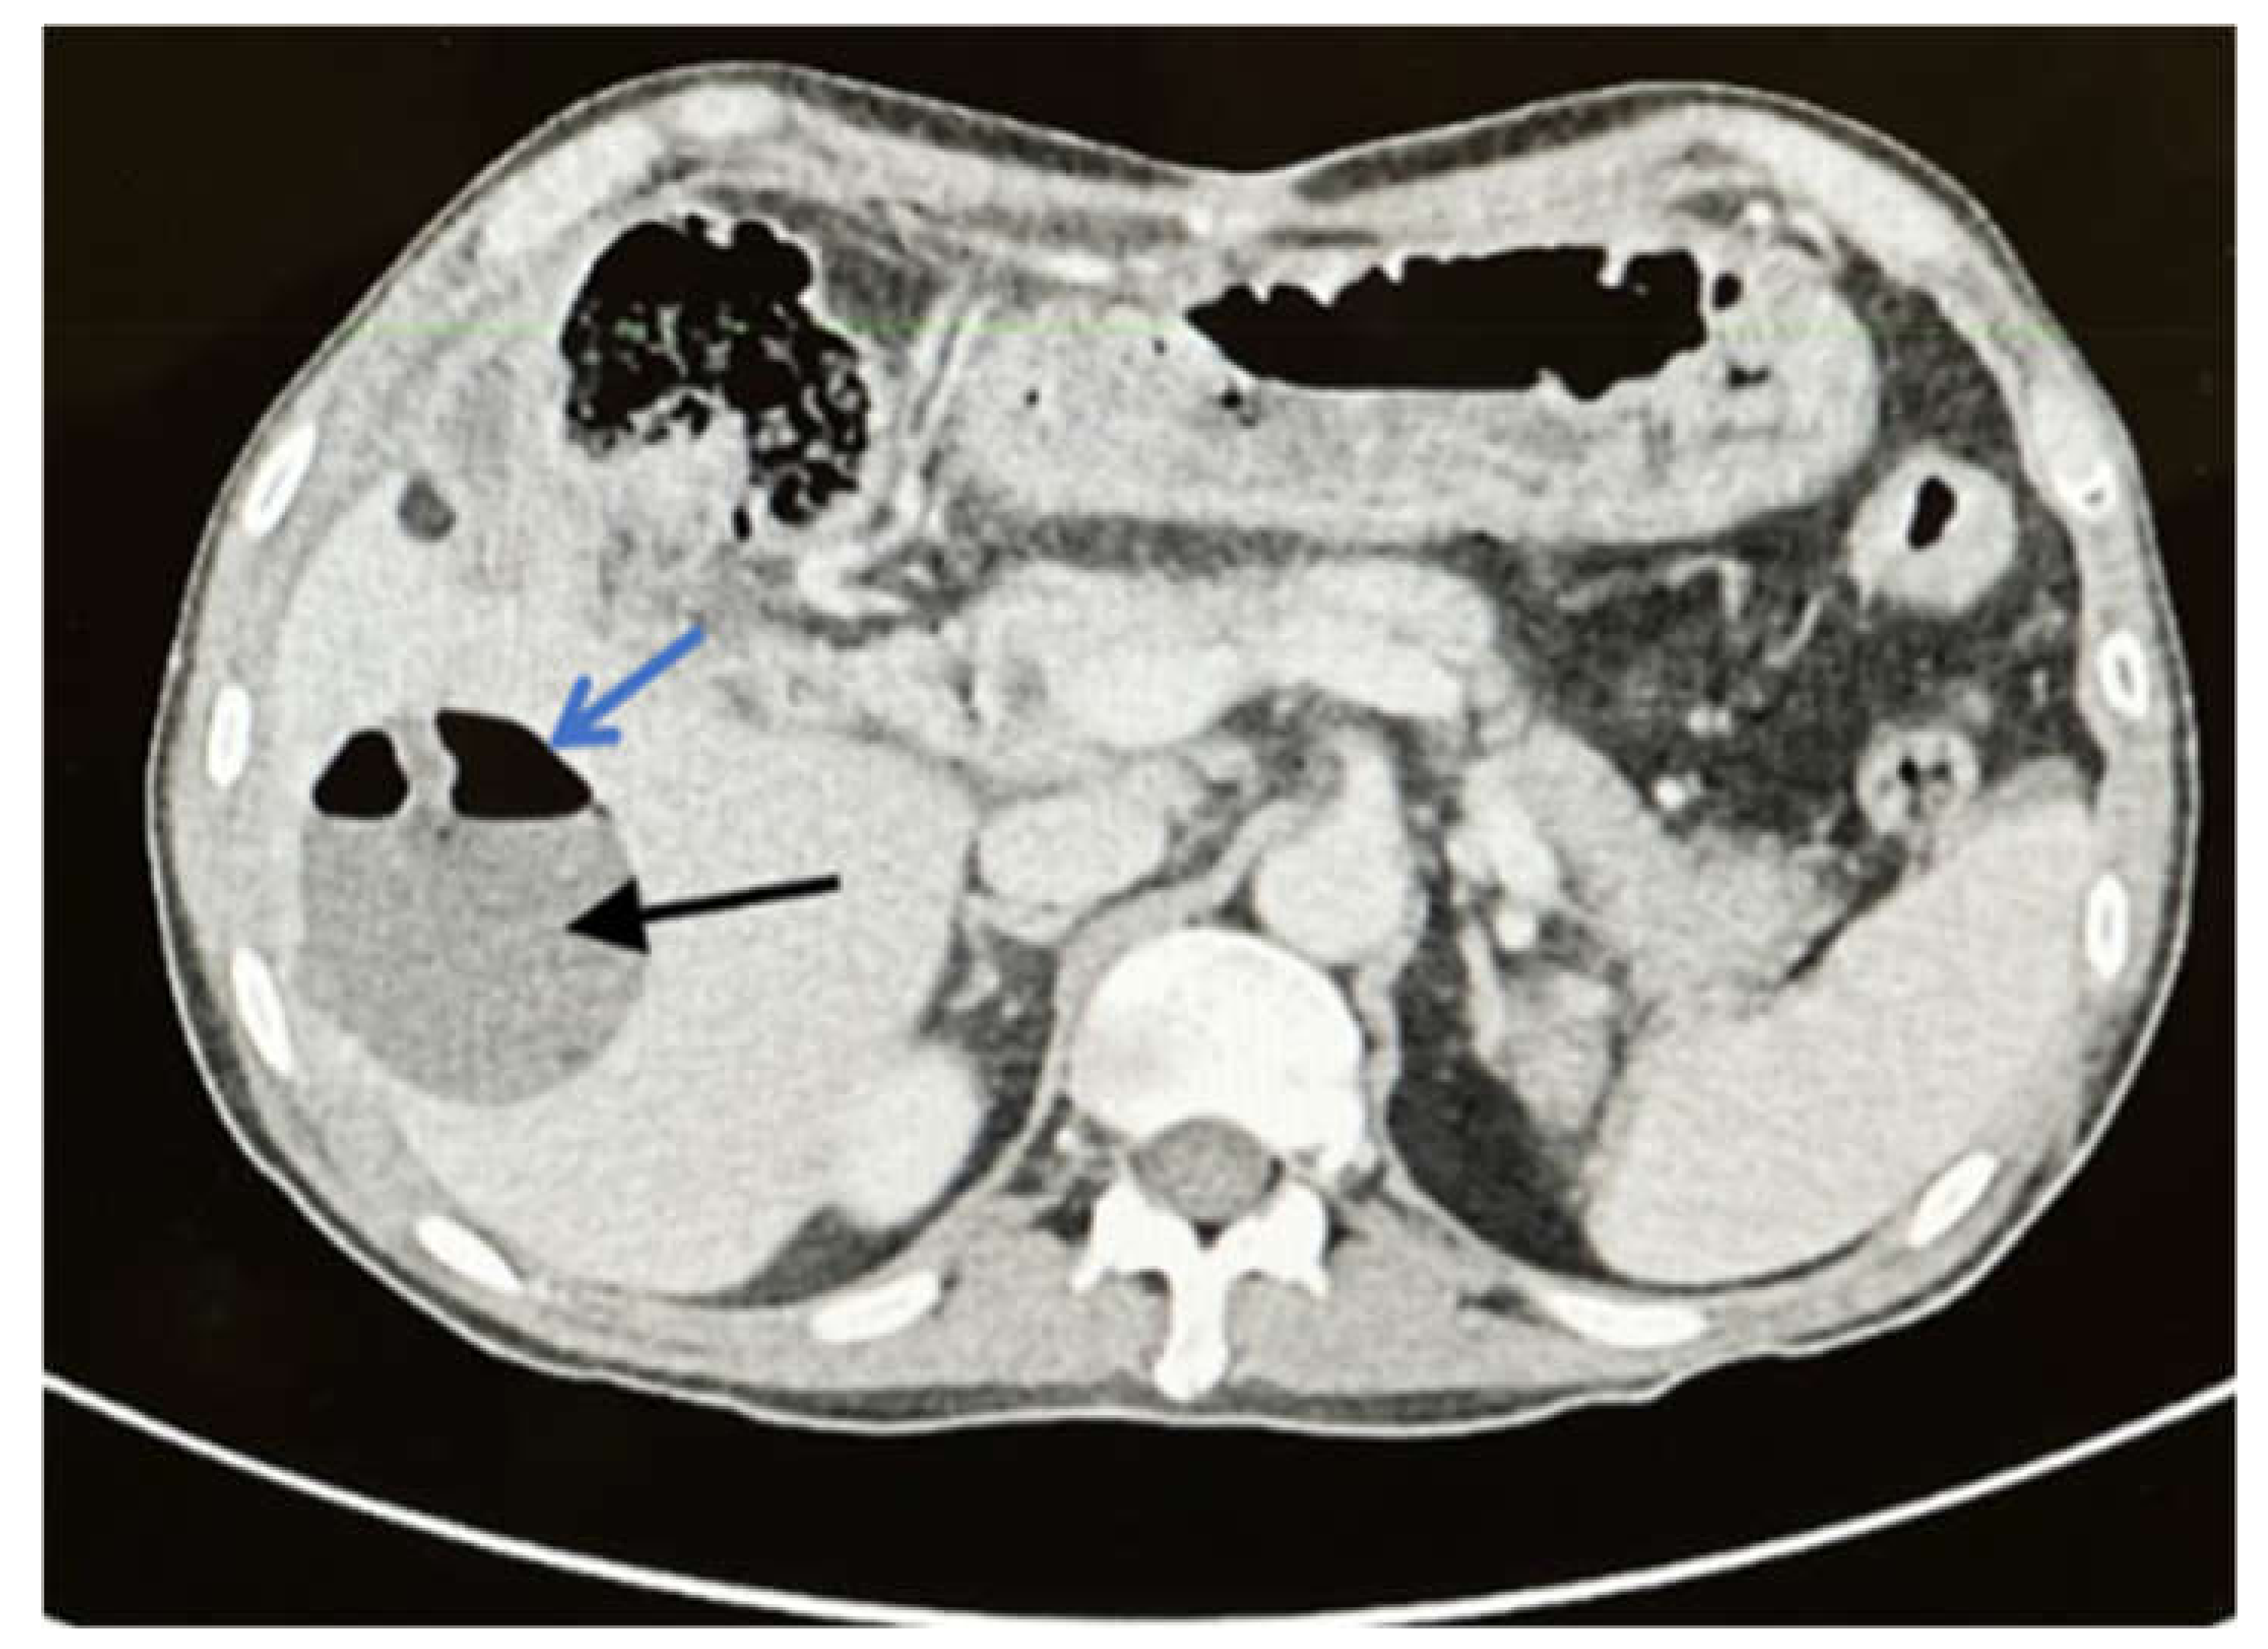

2. Case